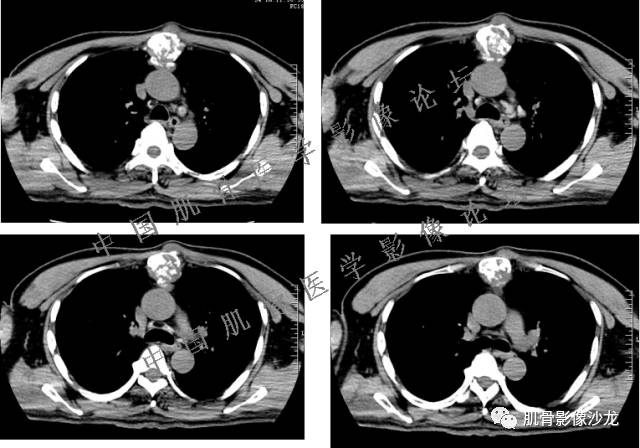

雪舞 :第二例,位于骶骨,有骨质破坏并有软组织肿块,软组织肿块边界清

向以四 : 病例2 感染性骶髂关节炎 TB可能大,左侧梨状肌受累、肿胀增粗,并见低密度脓肿?

西门吹雪:考虑恶性肿瘤 的确有些难

晴朗 :倾向肉瘤

医影在线 : 转移瘤要除外

致远 : 或者软骨肉瘤

张小林:炎性病变和肿瘤的鉴别

飞鹰行动 :有一定的骨质硬化,骨肉瘤及软骨肉瘤可能性大 晴朗: 有骨膜反应,有软组织肿块

雪舞: 第二例我们能够看到破坏与软组织肿块不成比例,软组织肿块大,破坏小

医影在线: 病变无明显钙化

雪舞 :第二例挺难的,骨质破坏是溶骨性的,局部皮质中断,软组织肿块外缘光滑

医影在线 :无软骨钙化

飞鹰行动 :有的软骨肉瘤可以没有钙化

晴朗 :软骨基质不一定都是钙化的

雪舞 : 软骨肉瘤的发病率居原发性恶性骨肿瘤的第三位,其特点是肿瘤内具有软骨基质

雪舞:弓形钙化,钙化比例少于面积的1/3,钙化边缘模糊

雪舞 : 都是软骨肉瘤鉴别于内生软骨瘤有意义的区别点